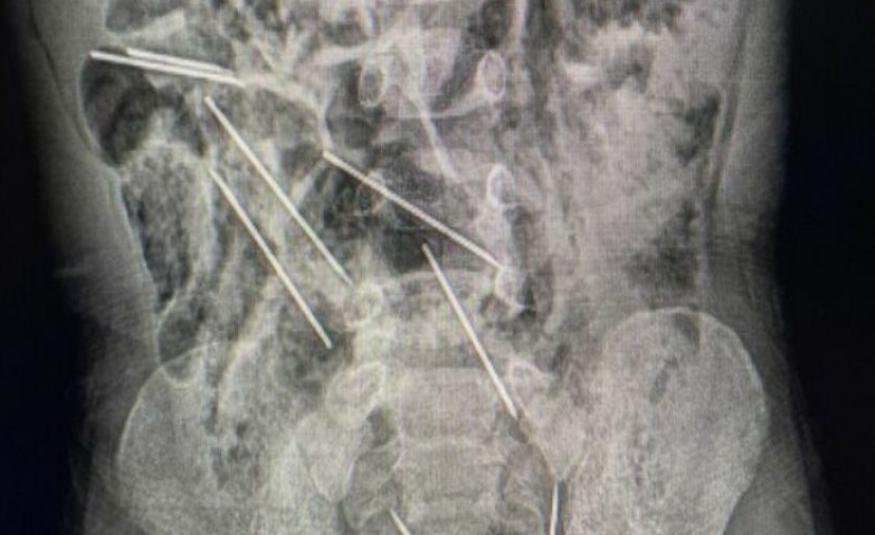

Dječak hitno prebačen u bolnicu: Progutao osam medicinskih igala, odmah operisan

Aktuelnosti Wed, 13 Sep 2023 - 09:25